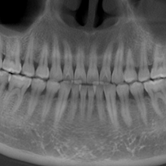

Dientes impactados

Los dientes impactados son dientes que no pueden erupcionar correctamente debido a la falta de espacio o a una obstrucción.

Los pacientes pueden notar que un diente no ha salido, aunque debería haberlo hecho. Esta condición es común con las muelas del juicio y los caninos superiores.

El tratamiento puede incluir la extracción del diente impactado o la creación de espacio para permitir su erupción.

Dientes Supernumerarios

Los dientes supernumerarios son dientes adicionales que pueden aparecer en la boca y causar problemas de alineación o erupción de otros dientes.

Los pacientes pueden notar dientes adicionales en la boca, lo que puede causar apiñamiento o problemas estéticos.

El tratamiento incluye la extracción quirúrgica de los dientes supernumerarios.